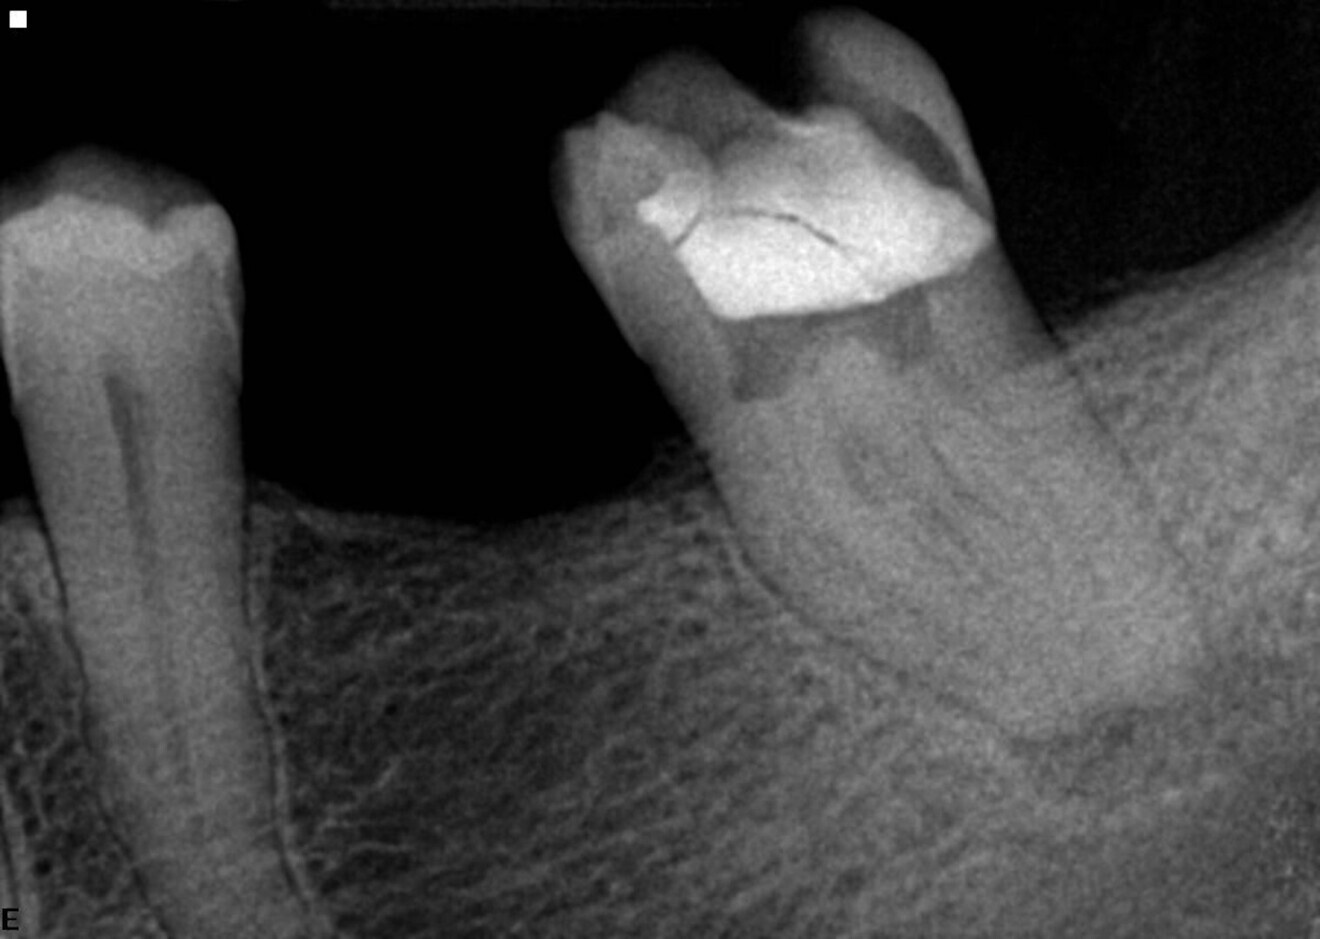

Maxillary second molars are in my opinion one of the most challenging teeth to treat because of their position and unpredictable anatomy. In this example case, the patient was referred for irreversible pulpitis (Fig. 5). Looking at the preoperative radiograph, we can see the curvature of especially the mesial and palatal root canals. The sequence used was as described before, starting with the 25/0.08 Traverse orifice opener as deep as it goes and just above the curve, followed by a 8 K-File for working length determination and the 13/0.06 Traverse file used to working length in all canals. During the use of the 13/0.06 Traverse file, I did not feel much resistance, so I decided to go ahead with the 0.06 taper sequence. The next file was the 20/0.06 ZenFlex, followed by the 25/0.06 ZenFlex file. Personally, I believe in apical enlargement, and for that reason, I used the 30/0.04 ZenFlex file as the final enlargement file in this case. I used a medium cone as the master cone and achieved 3D sealing of the system (Fig. 6). Of course, I performed complete chemical preparation, according to my sequence, during the procedure.

Fig. 5

Fig. 6